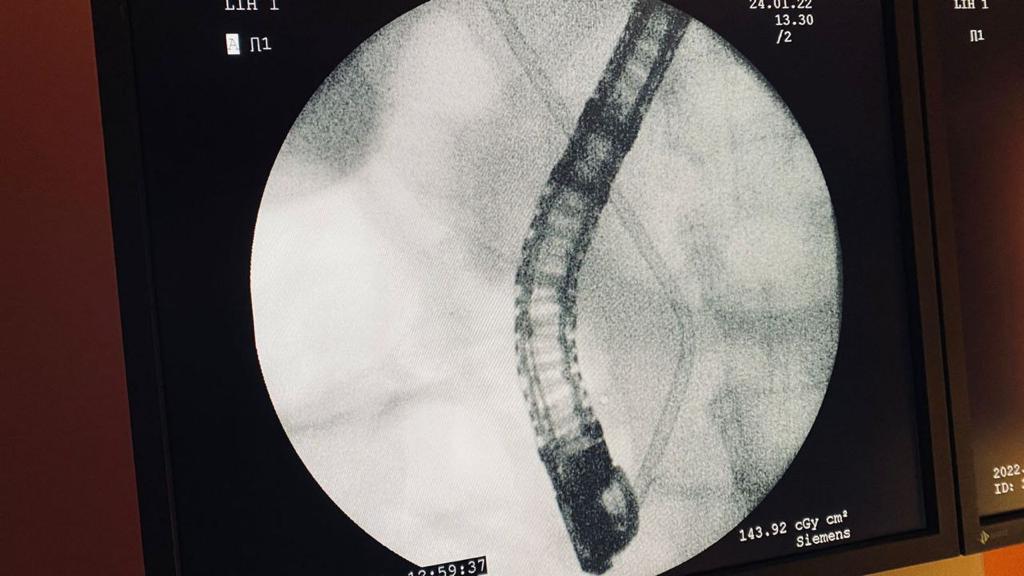

Врачи-эндоскописты Мангистауской областной больницы успешно провели первую эндоскопическую малоинвазивную операцию 69-летней пациентке с онкологией, сообщает пресс-служба Мангистауской областной многопрофильной больницы (МОМБ).

По данным пресс-службы, операция продолжительностью около часа была выполнена командой врачей: врачи-эндоскописты Елеусинов Роллан Серикович, Танауов Бауыржан Жоламанович, Тайшибай Максат Болатович, врач-хирург Мукантаев Талгат Естурганович, а также врач-анестезиолог Бултеков Сагадат Жексенгалиевич и медсестра-анестезист Зухра Сейтжанова.

- Пациентка 1953 года рождения поступила с диагнозом: «Опухоль головки поджелудочной железы. Механическая желтуха». Было проведено комплексное диагностическое обследование. У пациентки нарастала желтушность кожных покровов, острая слабость, печеночно-клеточная недостаточность, после чего женщина была госпитализирована в хирургический центр для оперативного лечения, - рассказал врач Бауржан Танауов.

В ходе дообследований был подтвержден диагноз «Механическая желтуха» - непроходимость желчевыводящих путей и желчного пузыря. Это состояние может быть вызвано наличием камней, кисты, скоплением паразитов, при опухолях печени, поджелудочной железы или желчного пузыря, при сужениях (стенозах) желчных путей. Было выявлено присутствие «блока» на пути поступления желчи в двенадцатиперстную кишку.

- Случай был рассмотрен на консилиуме врачей, по результатам которого было принято решение о выполнении эндоскопической малоинвазивной операции. Данная операция в нашей больнице проводилась впервые. Отток желчи был полностью восстановлен с помощью стентирования, за блоком мы установили дренаж (трубку), что позволило возобновить физиологический отток желчи в кишечник, поскольку вместе с желчью в кишечник попадают многие важные вещества, которые необходимы для нормальной жизнедеятельности организма, - сказал Бауыржан Танауов.

На данный момент пациентка проходит послеоперационный период, ей назначена специальная диета.